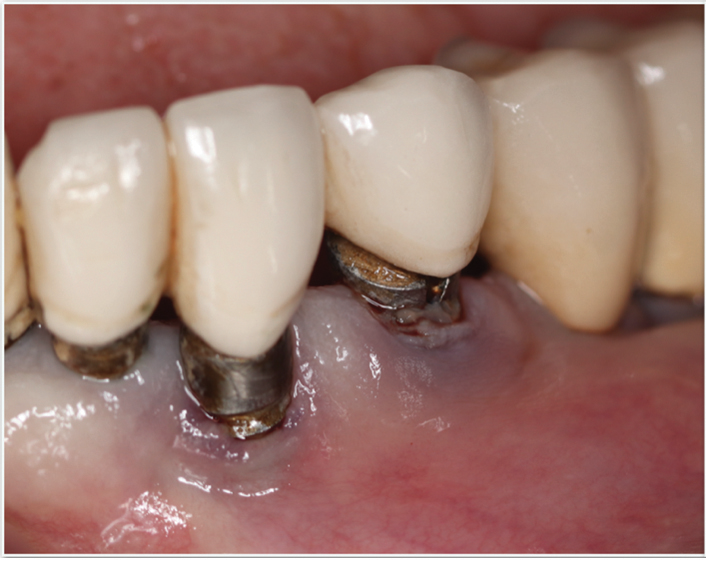

Fig 5 and Fig 6. Pre- (Fig 5) and post-treatment (Fig 6) photographs of a patient who received resective implant surgery to assess peri-implantitis at sites Nos. 14 and 15. Note the improved cleansability of the implants after surgery that opened the embrasure (Fig 6). The patient was placed on 3-month supportive peri-implant care post-surgery.

Figure 5

Figure 6

Surgical treatment encompasses both resective and regenerative approaches.41 During resective surgical therapy of peri-implantitis, the objectives are to remove excess granulation tissue, halt osseous cratering, and apically position the tissues, all of which may be done in combination with implantoplasty to smooth the threads of the roughened implant surface (Figure 5 and Figure 6).41 Conversely, regenerative surgical therapy involves the use of various combinations of bone grafts, membranes, and biologic materials to regenerate the lost implant-supporting structures.42